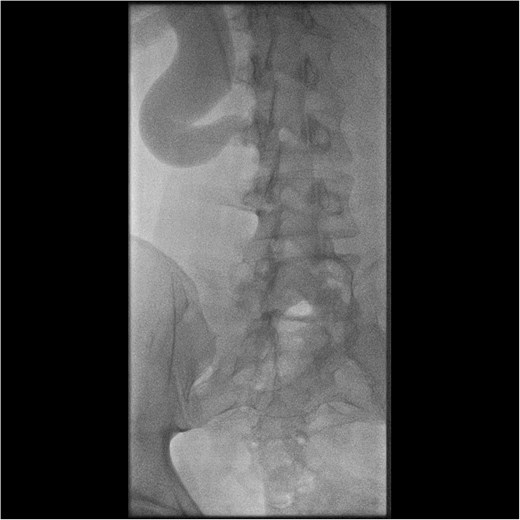

Initial work-up revealed microscopic haematuria and a mildly elevated creatinine of 156 μmol/L (65.4–119.3 μmol/L). A computerized tomogram (CT) urogram showed proximal hydroureteronephrosis with preserved renal cortex (Fig. 1). A diethylenetriamine pentaacetate (DTPA) renogram with diuretic showed accumulation of contrast then prompt excretion with administration of diuretic, suggesting partial obstruction or hypotonic collecting system (Fig. 2). At this point alternative diagnoses were considered, including RU. Ongoing severe right flank pain was noted despite multimodal analgesia and a right-sided nephrostomy was placed with immediate relief of pain and obstruction. Figure 3 shows the nephrostogram with S-shaped hydroureter. No further analgesia was required, and creatinine normalized (90 μmol/L). The case was discussed at a multidisciplinary meeting, wherein a unanimous diagnosis of RU was confirmed, and a plan for minimally invasive laparoscopic dissection and re-anastomosis of the ureter was made.

CT abdomen shows an S-shaped ureter with the right ureter passing behind the IVC.